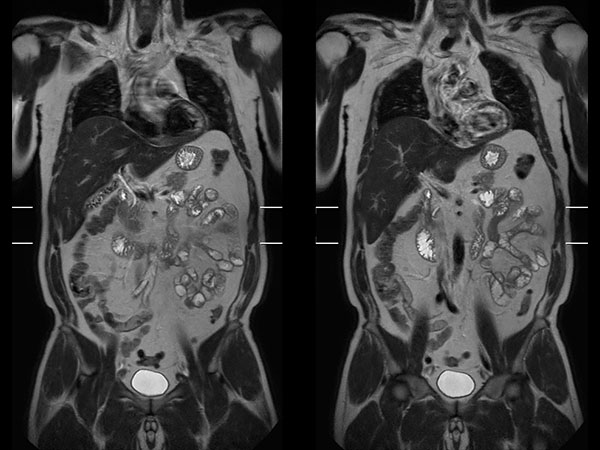

Total Torso imaging - MultiVane XD